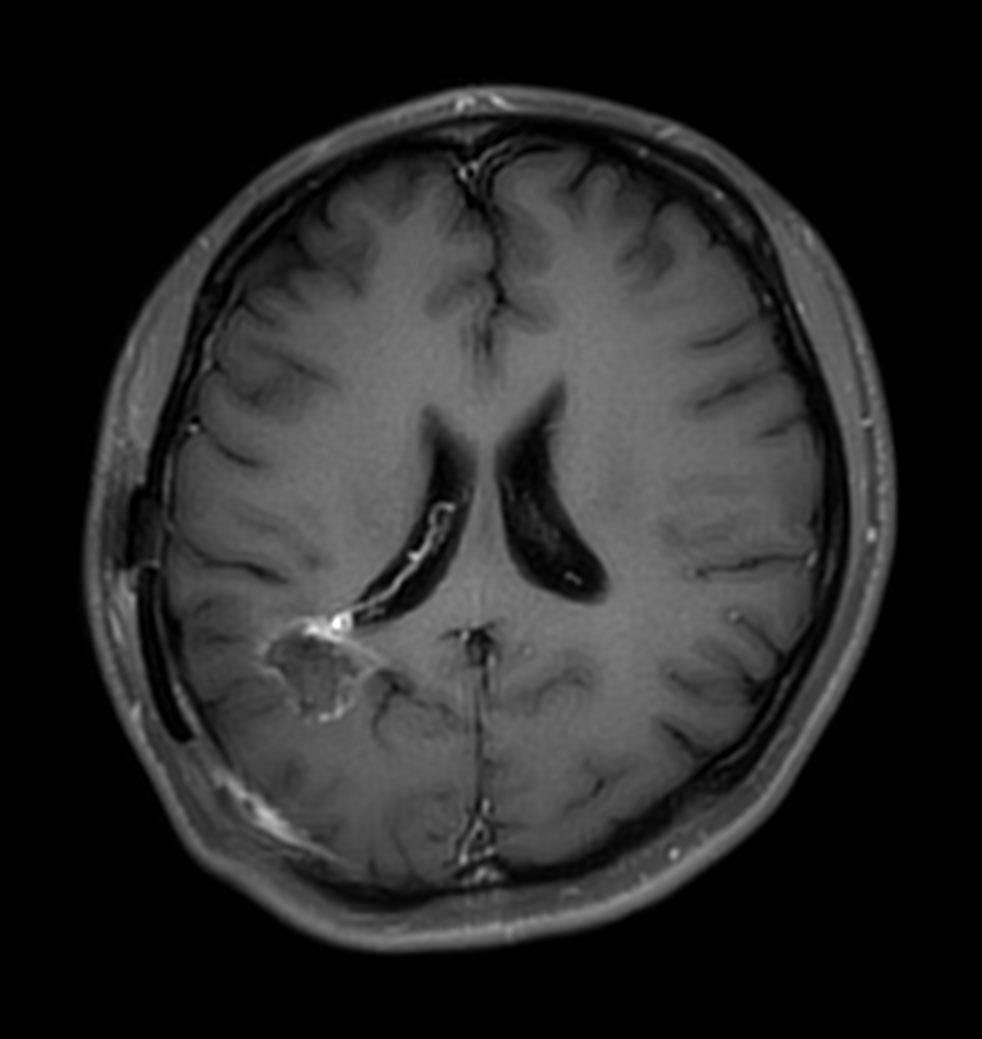

Axial T1w IR TSE with gado